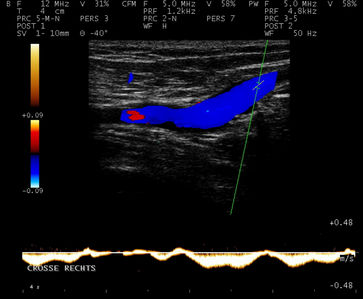

Sowohl die Funktion als auch die Morphologie der Venen können mit der Farbdopplersonographie beurteilt werden.

Normale Funktion der Mündungsklappe an der Einmündung der Vena saphena magna in die Vena femoralis